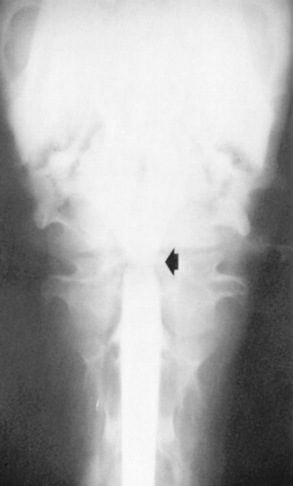

Survey radiographs of the cervical spine are obtained in standing, sedated horses. Cervical radiographs are evaluated by subjective assessment of vertebral malformation and objective determination of vertebral canal diameter.1878 The five categories of cervical malformation subjectively assessed in horses with CVSM are DJD of the articular processes, subluxation between adjacent vertebrae, flare of the caudal physis of the vertebral body, abnormal ossification patterns, and caudal extension of the dorsal laminae1878,1880 (Figs. 35-26 and 35-27). Although the presence of characteristic vertebral malformations supports the diagnosis of CVSM, subjective evaluation of survey radiographs does not reliably discriminate between horses affected and those unaffected by CVSM.1868,1878 DJD of the articular processes of the caudal cervical vertebrae is the most common and severe malformation observed in affected horses.1878 However, degenerative arthropathy occurs in 10% to 50% of nonataxic horses and is the most common and severe vertebral malformation in horses without CVSM.1869,1878 Subjective evaluation of degenerative arthropathy of the articular processes may lead to a false-positive diagnosis of CVSM.1868

Fig. 35-26 Survey radiograph of fifth (C5) and sixth (C6) cervical vertebrae. Bony malformations include flare of the caudal physis (curved arrow, C5), caudal extension of the dorsal lamina (small arrows, C5), and subluxation and malalignment of the C5-C6 articulation. Solid line, Intervertebral canal diameter of C5-C6 articulation; double-headed arrow, intravertebral canal diameter of C5.